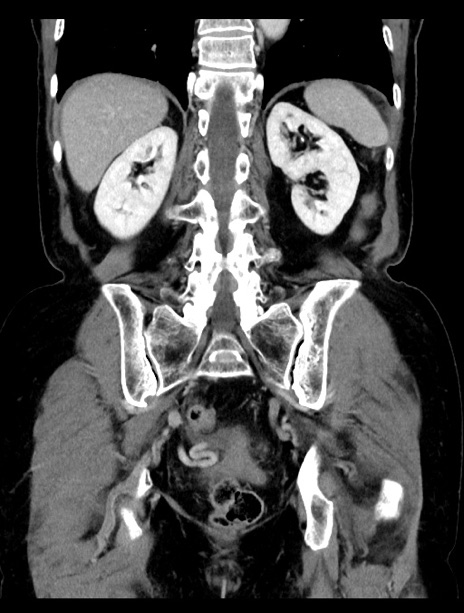

症例23(冠状断像)

【症例】70歳代女性

【主訴】下腹部痛・嘔吐

【現病歴】2日前より腹痛あり。昨日嘔吐あり。症状改善しないため来院。

【既往歴】胃GISTに対して胃部分切除後。

【身体所見】BT 37.1℃、BP 128/77mmHg、腹部:平坦・軟、下腹部に圧痛あり。

【データ】WBC 10200、CRP 0.31